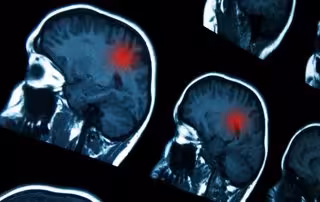

Un estudio revela la principal diana de la COVID-19 en el cerebro y describe sus efectos en el sistema nervioso

Un estudio brasileño publicado en la revista 'PNAS' ha revelado la principal diana de la COVID-19 en el cerebro y ha descrito algunos de los efectos que la infección por el SARS-CoV-2 puede tener en el sistema nervioso central.

La corteza cerebral es la capa exterior de materia gris que recubre los hemisferios. Es el mayor lugar de integración neuronal del sistema nervioso central y desempeña un papel clave en funciones complejas como la memoria, la atención, la conciencia y el lenguaje.